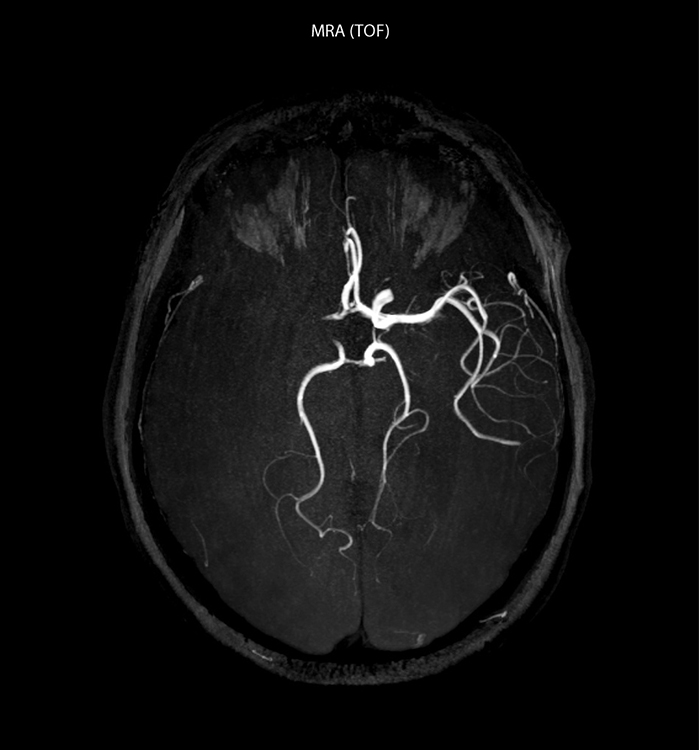

“In France, stroke is usually imaged with MRI, not CT, even for emergency treatment. This is because MRI helps us directly visualize ischemia in the acute phase, but can also help rule out differentials such as MS and hematoma. In addition, we can assess the intracranial and extracranial vessels during the same examination,” says Dr. Savatovsky.

“Ingenia provides great flexibility in the parameters setting. We can tune a sequence the way we want,” says Dr. Savatovsky. “For example, in a stroke exam we use a FLAIR sequence of about two minutes instead of the four-minute FLAIR we use for MS. The diffusion is 30 seconds, the T2*-weighted scan is 30 seconds, the angiography scan time is less than one minute. Ingenia is a great scanner in that situation; even with these fast sequences we can achieve good images with good SNR. When the first sequence tells us that it’s not an ischemic stroke but a hemorrhagic stroke, we may switch to a time-resolved angiography to look for vascular malformations and venous thrombosis.

The ideal stroke protocol?

“Every center is different, but for me the ideal protocol for stroke includes diffusion weighted imaging, FLAIR, and fast susceptibility imaging,” says Dr. Savatovsky. “Our fast susceptibility weighted imaging takes 50 seconds, so it’s as fast as T2*-weighted imaging. It visualizes hemorrhage but also the clots. We also do 3D MR angiography that provides information on cervical and brain vessels. If the patient does not need immediate treatment, or if additional information is needed to decide on treatment, we might also add perfusion imaging and post-contrast T1-weighted imaging.”